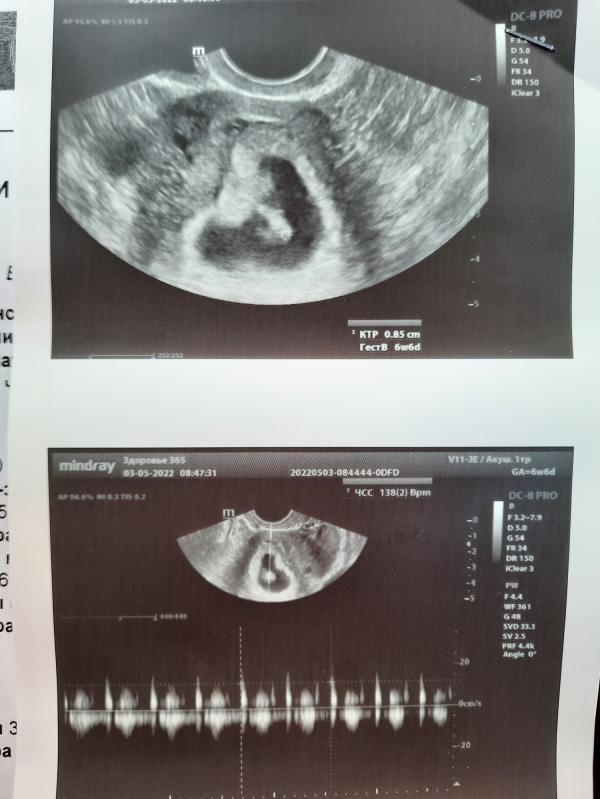

Гипертонус на 6-7 неделе беременности: что делать, Дюфастон помог? Отзывы и сердцебиение

Ну всё)) это точно не глюк))

6-7 неднля по узи и размеру плода.

Ставят гипертонус прописали Дюфастон.

Но в остальном всё хорошо.

Боже я заревела когда услышала сильное уверенное сердцебиение 💓